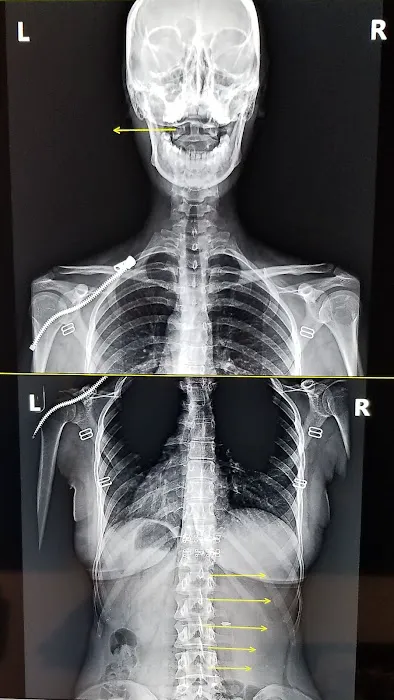

Chiropractic Health Center Photos